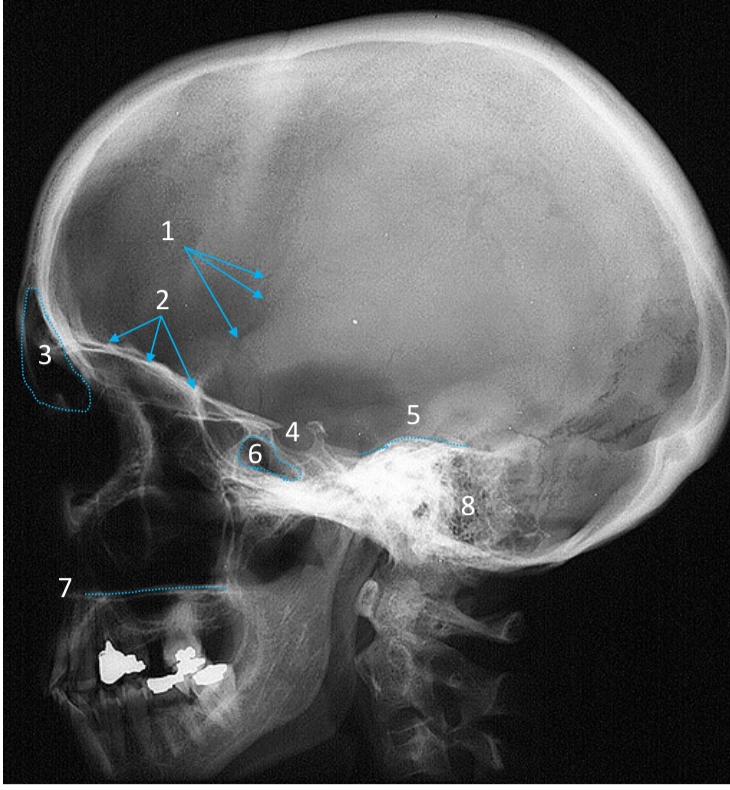

Mandible

ID bone

Maxilla

ID bone

Frontal sinus

ID structure

Pituitary fossa

ID structure

Occipital

ID bone

Lambdoid suture

ID structure

Frontal sinus

ID structure

Orbital margin

Orbit

Maxillary sinus

ID structure

Mandibular condyle

ID structure

Inferior nasal concha

ID structure

Hard palate

ID strucutre

Gonial angle

ID strucutre

Petrous ridge

ID structure

Groove of middle meningeal a.

ID structure

Roof of orbit

ID structure

Frontal sinus

ID structure

Pituitary fossa

ID structure

Petrous ridge

ID structure

Sphenoid sinus

ID structure

Hard palate

ID structure

Mastoid air cells

ID structure

Zygomatic arch

ID structure

Mandibular condyle

ID structure

External auditory meatus

ID structure

Mastoid air cells

ID structure

Foramen magnum

ID structure

Foramen ovale

ID structure

Foramen spinosum

ID structure